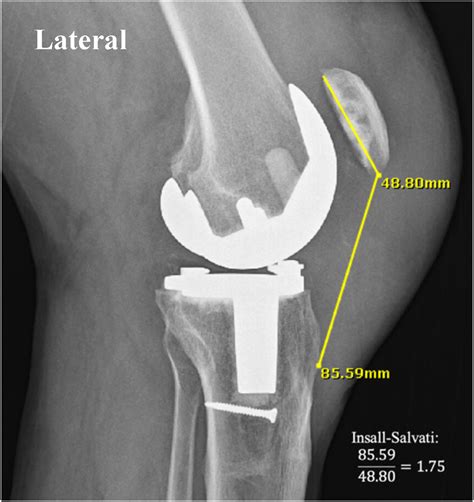

• Imaging Tests: X-rays, ultrasound, and MRI scans can provide detailed images of the knee and help confirm the diagnosis. MRI is particularly useful for assessing the extent of the tear and planning treatment.

• patellar tendon rupture x ray